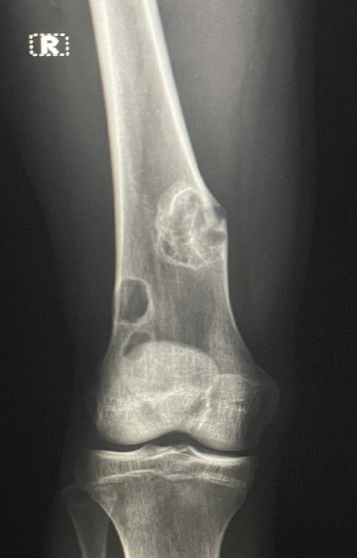

Letter to the Editor: Revisiting the “Ice Cream Scoop” Sign in Adult Elbow Tuberculosis: Extending Beyond the Pediatric Population

Nadeem Akhtar Qureshi

………………………………p.555-556